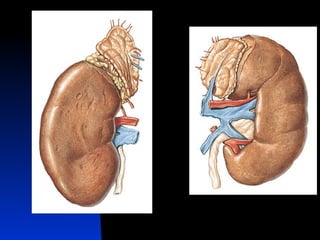

Néfron     Unidade funcional Função de filtragem do sangue, retorno de substancias úteis para o sangue, mantêm a homeostasia de sangue.    Cerca de 2 milhões nos dois rins

Partes do NéfronCorpúsculo renal: onde o plasma é filtrado. Contem o Glomérulo e a cásula glomerular ( de Bowman) Tubulo renal: pelo qual passa o liquido filtrado.